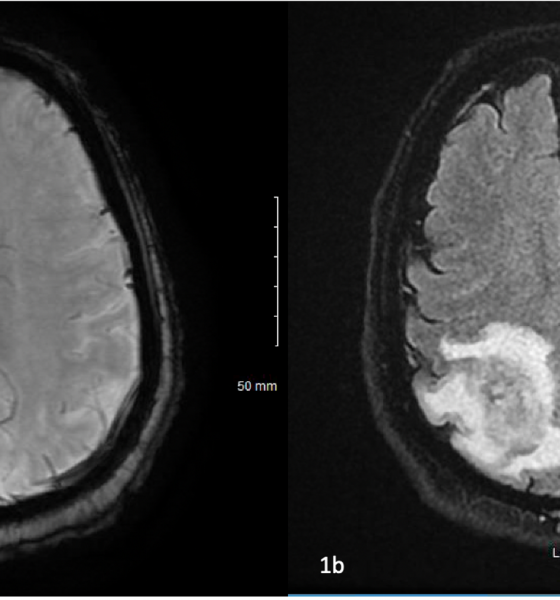

Betim GashiNokardioza është një infeksion i rrallë që fillon në mushkëri dhe më vonë mund të përhapet në lëkurë dhe tru. Ky është një infeksion bakterial i shkaktuar nga bakteri Nocardia asteroides i cili transmetohet nga pluhuri i tokës së ndotur.

Nocardia gjendet në tokë, bimësi në prishje dhe disa lëndë organike, si dhe në ujë të freskët dhe të kripur. Ai hyn në trup duke thithur ajrin në të cilin është i pranishëm bakteri, dhe gjithashtu përmes një plage të hapur. Nuk transmetohet nga njeriu te njeriu, por është më i zakonshëm te pacientët me një sistem imunitar të dobësuar për shkak të sëmundjeve të tilla si kanceri, diabeti, HIV ose AIDS.

Simptomat e nokardiozës varen nga pjesa e trupit që preket nga bakteri. Këto janë më shpesh mushkëritë, por simptomat mund të ndodhin edhe në lëkurë, sistemin e tretjes, trurin, veshkat, zemrën, sytë ose kockat.

Me këtë nokardiozë mund të ndodhë ethe, dobësi, dhimbje gjoksi, kollë, humbje e oreksit dhe djersitje natën. Gjithashtu, mund të ketë një akumulim të lëngjeve në mushkëri, por edhe pneumoni.

Në varësi të zonës së trupit, mund të ndihen shqetësime të ndryshme si dhimbje, të përziera, të vjella ose ënjtje, dhe nokardioza në tru mund të çojë në kriza, dhimbje koke ose marramendje.

Meqenëse simptomat e nokardiozës mund të tregojnë ndonjë sëmundje, do të jetë e nevojshme të bëni një seri testesh. Këto përfshijnë rrezet X të mushkërive, bronkoskopinë, biopsitë e mushkërive, trurit ose lëkurës, si dhe ekzaminimet e organeve në të cilat u shfaqën simptomat.